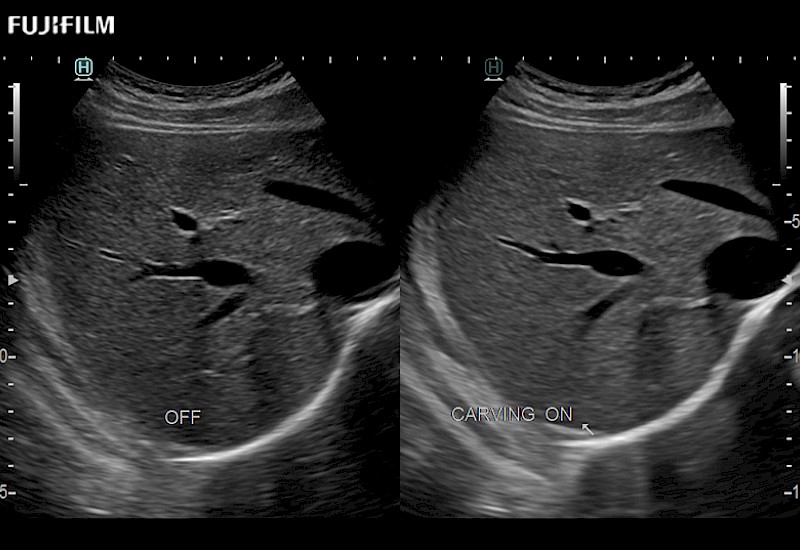

The ARIETTA 750 incorporates all of the proven technologies and functions that medical professionals have come to expect from Fujifilm Healthcare.

ARIETTA 750 is the definitive diagnostic ultrasound solution for any clinical setting - Private Office, Imaging Center, or Hospital. The ARIETTA platform provides the ultimate in clinical performance with its state-of-the-art features and large user-friendly display.

The ARIETTA 650 DI combines trusted Fujifilm Healthcare technologies and features tailored for surgical oncology.

Designed to meet the demands of surgeons, the ARIETTA 650 DI offers precise guidance. Its advanced capabilities and large, intuitive display offer accurate and efficient care in operating rooms and specialized surgical settings.